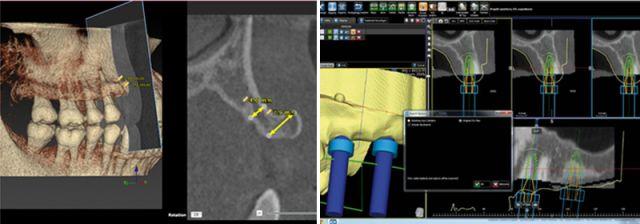

種植牙目前好選擇先進(jìn)的3D數(shù)字化全程導(dǎo)板種植牙技術(shù),根據(jù)數(shù)碼掃描,骨骼、神經(jīng)、血管等組織的三維模型重建,設(shè)計(jì)種植位置,選定合適的種植體,完全模擬顯示種植體在牙槽骨的位置,打印出導(dǎo)板模型,利用導(dǎo)板,確立種植體與牙頜竇底的距離、深度、種植體半徑、傾斜度等,按照種植導(dǎo)板導(dǎo)航種植,減少種植手術(shù)的時間,手術(shù)過程全程!華南目前在能開展這項(xiàng)技術(shù)的醫(yī)院中德倫口腔首屈一指。